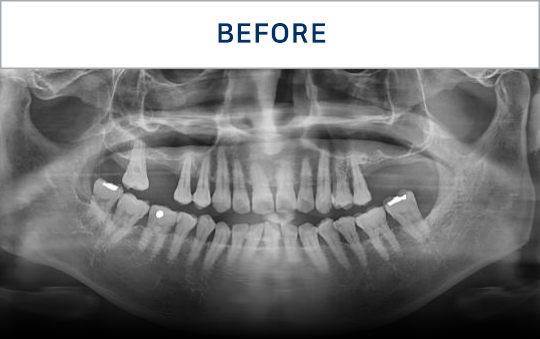

전후가 명확한 결과, 그 결과가

곧 신길플란트치과의 신뢰입니다.

불편함 없이 웃고, 걱정 없이 드실 수 있도록 임플란트로 일상의 편안함을 되찾아드리겠습니다.